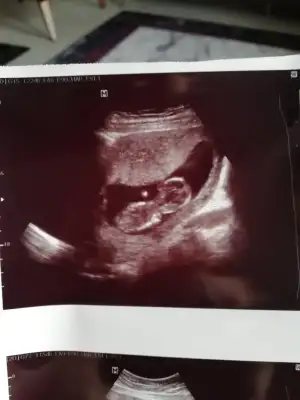

Erkek gibi 12+ yada 13 hafta paylaşınIkra meyra yorumunuzu alabilir miyim![]()

Tmm o zaman kontrole gidersek paylaşırım inşallahErkek gibi 12+ yada 13 hafta paylaşın

11 12 13 haftalar nub için uygun şimdilik sanki erkek gibi gibi dediğimiz usgleri paylaşırmısınızIkra meyra bir bakarmısın canım

Malesef bir tek bu var 11+5 olarak başka yok11 12 13 haftalar nub için uygun şimdilik sanki erkek gibi gibi dediğimiz usgleri paylaşırmısınız